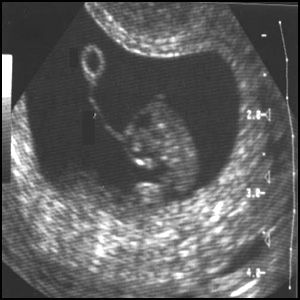

Так может поосторожничать и делать УЗИ только в крайнем случае? Недаром же ребёнок, «плод», шарахается в сторону от ультразвукового датчика, пытаясь скрыться от него. Это же хорошо видно на дисплее. Всем хочется жить, и ребёнку тоже.

УЗИ – исследование, с которым сталкивается каждая беременная женщина. В наше время принято считать его безвредным, стало модно часами записывать видео в кабинете диагностики. Но так ли безобидно УЗИ и что думают об этом наши малыши? Давайте рассмотрим подробнее все эти вопросы.

Очень нелепо получается – мы делаем УЗИ, чтобы убедиться в том, что малыш здоров, и тем самым причиняем ему волнения, а возможно и боль... Мое мнение – делать УЗИ не более 3 раз за срок, не ранее 12 недель и только двумерное. Без записи на диск – для экономии времени воздействия.